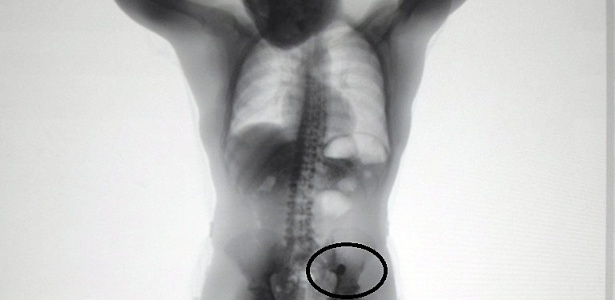

Agentes da SAP (Secretaria da Administração Penitenciária) de São Paulo acharam duas alianças dentro da barriga de um homem que tinha sido preso suspeito de assaltar um casal. O objeto só foi descoberto quando o detento passou pelo detector de metais do CDP (Centro de Detenção Provisória 4) de Pinheiros, na zona oeste da capital paulista, após passar pela audiência de custódia no último dia 9 de maio.

O detento, identificado pela pasta apenas como C. S. Q., passava pelo scanner corporal ao qual os presos são submetidos quando dão entrada na unidade quando os agentes viram os dois anéis de outro no lado esquerdo do abdômen do homem. Segundo a SAP, ele confessou ter engolido o objeto e que se tratava de um par de alianças.

Ele foi levado à enfermaria do CDP e ficou isolado no local até expelir os dois objetos.